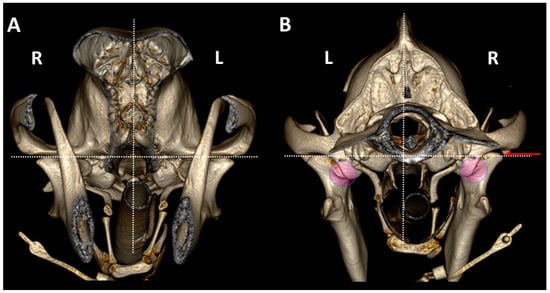

3.1. A Detailed Description of the Bone Anatomy of TMJ Using 3DVR Images

3.2. Comparison by 3DVR of TMJs in Each Dog, According to Skull Type and Age